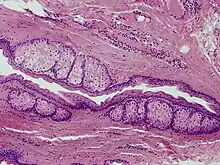

Steatocystomas are thought to come from an abnormal lining of the passageway to the oil glands (sebaceous duct).